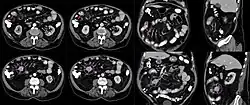

Primärtumor und Metastasen werden sonografisch, mit Computertomographie (CT), Angiografie oder Endoskopie nachgewiesen. Möglich ist auch die Octreotid-Szintigrafie, da das Karzinoid diese Rezeptoren aufweist. Mit neueren nuklearmedizinischen Nachweismethoden, vor allem mit PET (meist mit einem CT gekoppelt), wird derzeit intensiv versucht, die oft sehr kleinen Tumorherde in einem möglichst frühen Stadium zu erkennen.